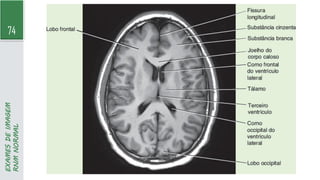

74

RNM

NORMAL

73 EXAMES DE IMAGEM RNM COM AVC ► RNM: técnicamais sensível, pois detecta AVCi em minutos após a sua instalação por meio da técnica de difusão - padrão ouro: RNM com difusão, mostrando hipersinal e o MAPA-ADC (coeficiente aparente de difusão) com hipossinal no local do infarto - alterações permanecem até 4 semanas no exame por meio de difusão ► Sequência FLAIR (inversão-recuperação com atenuação de fluido): alterações surgem após 4,5h após início dos sintomas - importante p/ determinar momento que déficit teve início (paciente teve AVC dormindo)

• 74.